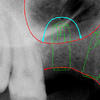

Ilyen a digitális röntgen és képelemző rendszer. Ennek egyik előnye a hagyományos röntgenhez képest, 90%-kal kisebb sugárterhelés, amely még nagyobb felvételszám vagy kismamák esetében sem jelent a szervezet számára megterhelést. Másrészt, a szokásos röntgenfilmnél akár 50-100-szor nagyobb képátmérőnek köszönhetően a legapróbb részletek sem maradnak észrevétlenek, ami még pontosabb diagnózist eredményez. A felvételek számítógépes elemezésével alaposabb kezelési tervet lehet készíteni, sőt, amint az a képeken is látható, az ellátás modellezésére és akár menet közben történő ellenőrzésére is lehetőség van.